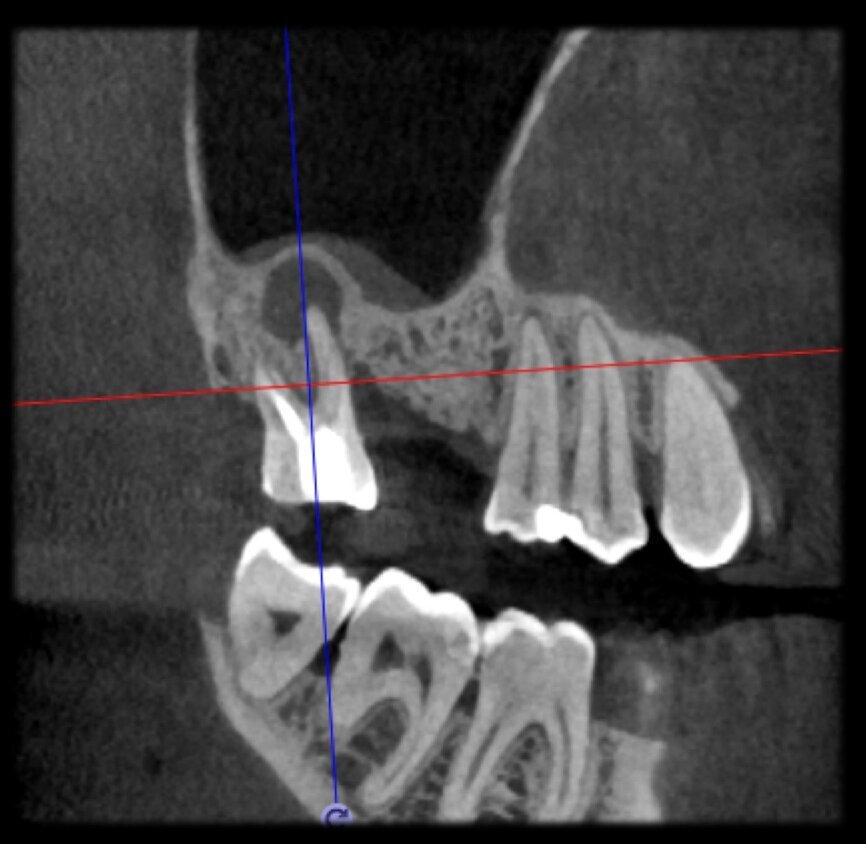

The case with which I would like to start my clinical review is a perfect example of how difficult it is to establish the origin of the patient’s symptoms on the basis of an intraoral radiograph alone. Not only does the 2D study fail to establish with certainty the presence of a lesion, but more importantly, it is impossible to establish the size, morphology and type of the lesion. An analysis of the 3D imaging, however, provides a clear picture of the clinical situation: the coronal and sagittal slices revealed the presence of a large lesion extending from the apex of the mesial root of this molar to the furcation, while the axial slices allow us to conduct a precise analysis of the endodontic anatomy and, in particular, the shape of the mesial root, which in this case was fused with the palatine root. A full overview of the case can, therefore, guide the decision-making process and direct the treatment plan towards a specific type of treatment (Figs. 1–4).